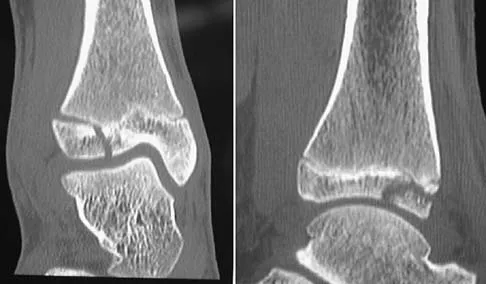

A 13-year-old girl injures her ankle playing soccer. Radiographs reveal a displaced Tillaux fracture. CT scans are shown in Figure 25. What is the most important consideration for appropriate management?

Explanation

The correct starting point for an external fixation half pin placed into the anterior inferior iliac spine (AIIS) is labeled by what letter in Figure 3?

Explanation